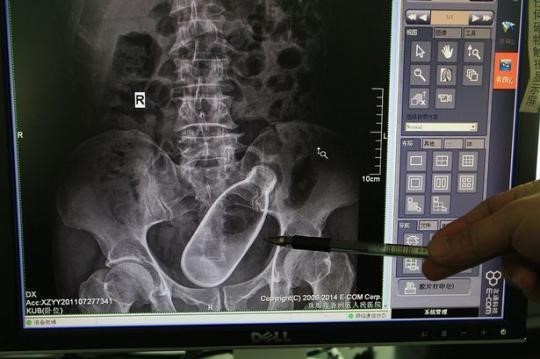

병원 진료를 받게 된 남성은 엑스레이 촬영을 하였으며 엑스레이 사진에는 20cm 길이의 덤벨이 직장과 결장이 만나는 곳에 박혀있는 모습이 포착되었습니다.